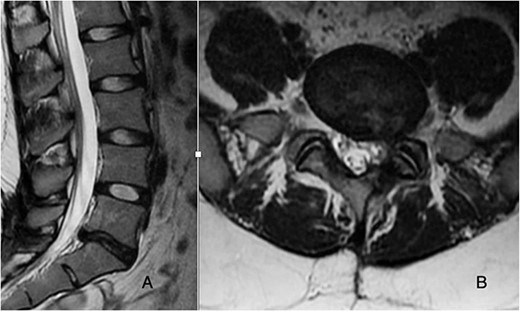

Preoperatively, her physical exam demonstrated left-sided quadriceps weakness and minimally diminished sensation in an L3-L5 distribution. The patient’s magnetic resonance imaging (MRI) demonstrated degeneration of the L5-S1 disc with disc height loss and left-sided L5-S1 foraminal stenosis (Figs 1 and 2).

T2-weighted MRI sagittal and axial cuts demonstrate recurrent disc herniation with left-sided foraminal stenosis and degenerative changes at L5-S1.